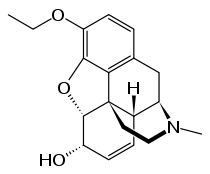

Several semi-synthetic opioids were developed in Germany in the 1910s. The first, oxymorphone, was synthesized from thebaine, an opioid alkaloid in opium poppies, in 1914.[228] Next, Martin Freund and Edmund Speyer developed oxycodone, also from thebaine, at the University of Frankfurt in 1916.[229] In 1920, hydrocodone was prepared by Carl Mannich and Helene Löwenheim, deriving it from codeine. In 1924, hydromorphone was synthesized by adding hydrogen to morphine. Etorphine was synthesized in 1960, from the oripavine in opium poppy straw. Buprenorphine was discovered in 1972.[228]